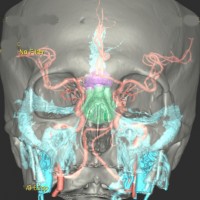

頭蓋骨を透して下垂体腺腫を見たものです。両目の間,頭の中心に緑色に塗ったのが下垂体腺腫です。頭蓋底の鼻腔の奥にあるともいえます。赤い色は動脈,青い色は静脈で,多くの血管に囲まれています。

下垂体へ到達するには,黒い矢印のように鼻の孔からのぞいて鼻腔を通って,空色に塗った蝶形骨洞というところを通っていくので,これを経蝶形骨洞手術 transsphenoidal surgery TSSと言います。下垂体腺腫にもっともよく用いられる手術法です。気をつけなければならないのは,海綿状脈洞に伸びている腫瘍を手術で摘出しようと言われたときです。海綿静脈洞内部の手術は開頭手術になることもあり危険性は高いといえます。時には死亡例もあるので手術の内容はしっかり聞いて下さい。

左は下垂体腺腫(緑の腫瘍)が内頚動脈に挟まれていることを示しています。